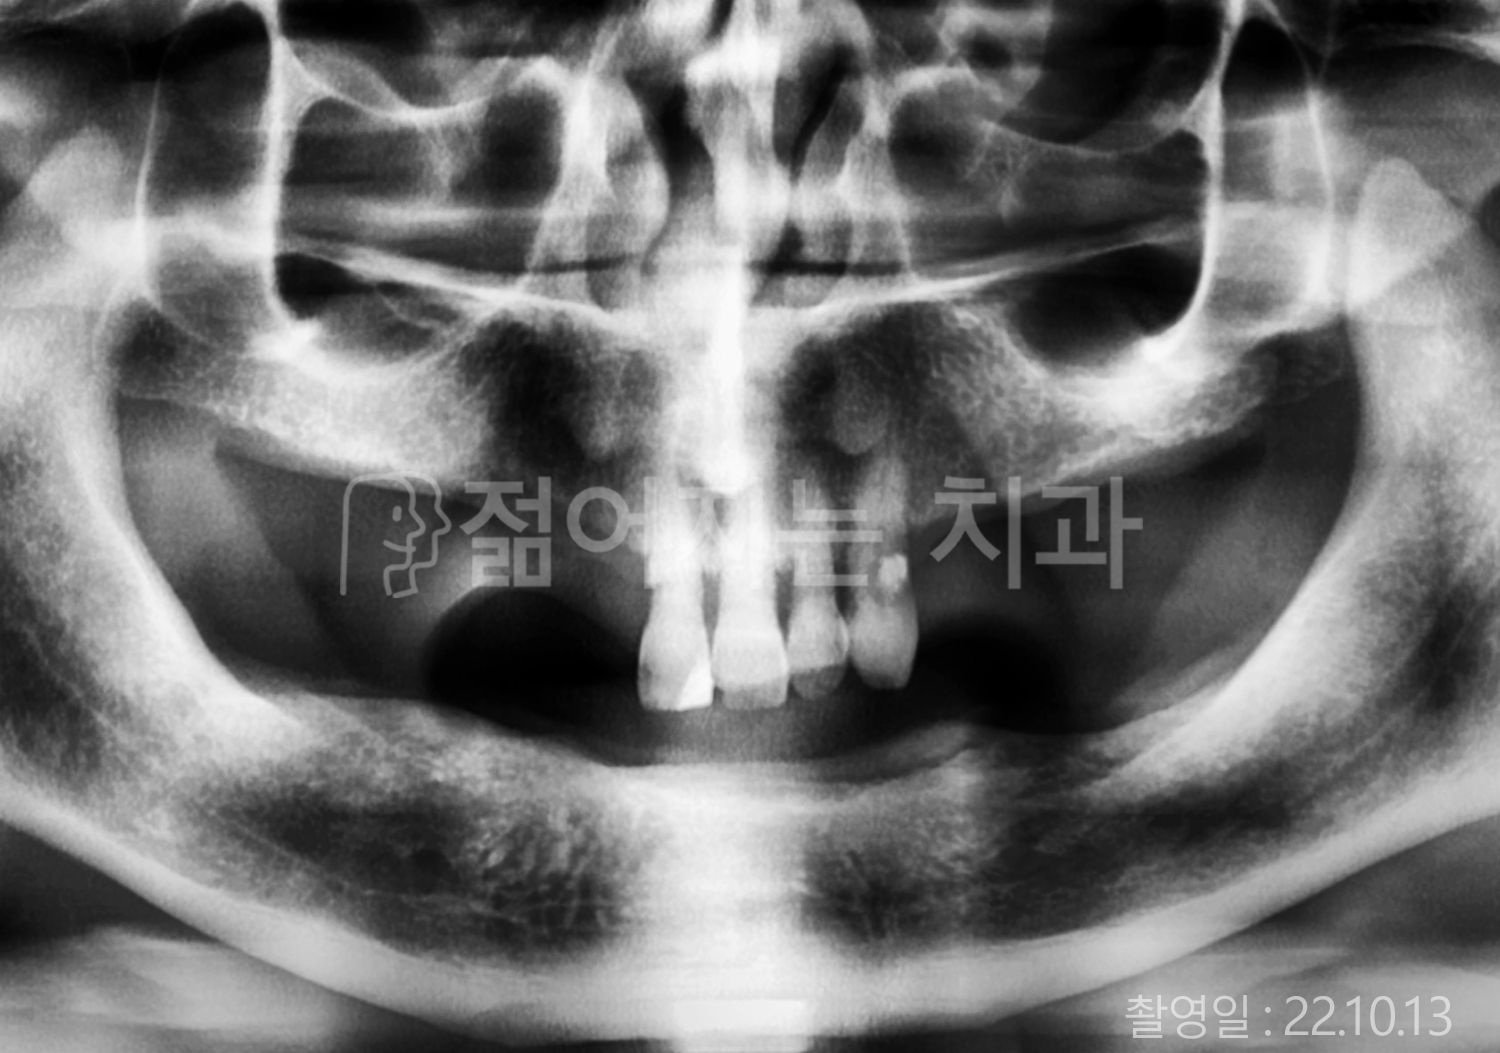

• 70대 고혈압, 고지혈증 전체치아 10개 이상 임플란트

• 60대 당뇨, 간염 전체치아 10개 이상 임플란트

• 80대 골다골증 전체치아 6개 이상 임플란트

• 70대 고혈압, 당뇨 전체치아 10개 이상 임플란트